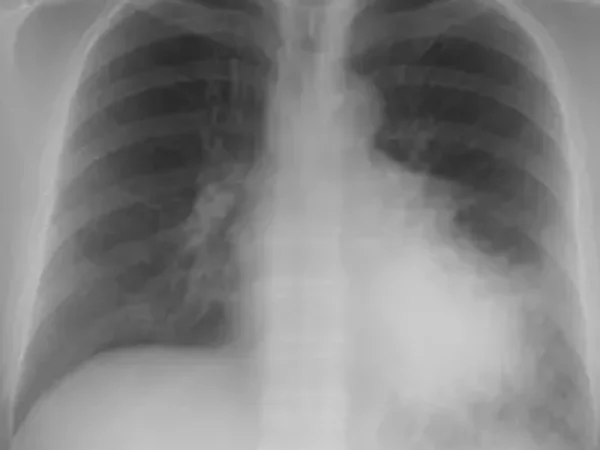

Learn how to diagnose and manage aspiration pneumonia in the ED with a twist. There's a board test answer and a "real life" answer for this one…Let's talk risk factors, key imaging findings, antibiotic choices, and when to worry.